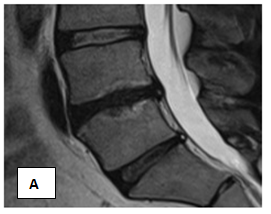

In the period from May to June 2015, patient S. was given a course of MFVVT from 15 procedures. During the first week, the patient's condition stabilized, pain and irradiation in the limb decreased, antalgic scoliosis is not detected, a symptom of tension of 50 degrees. By the end of the course of treatment, the patient's condition is good, there is no pain in the lower back. Preserve the area of ​​numbness in the left foot. Inspection after 2 months did not reveal pathological abnormalities. MRI from 27.08.15. (Figures 4A & 4B). Drive L 4-5: moderate decrease in disc height and intensity MR - signal. Op. posterior protrusion of the disc up to 4mm. Bone swelling of adjacent vertebrae.

Figure 4 Patient S. After the course of MFUVT.